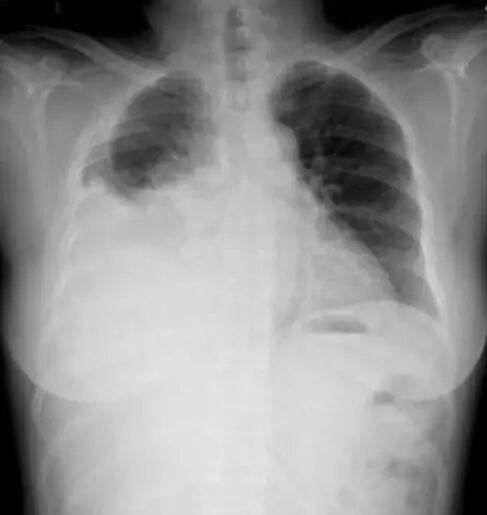

⑥出现胸水或心包积液;